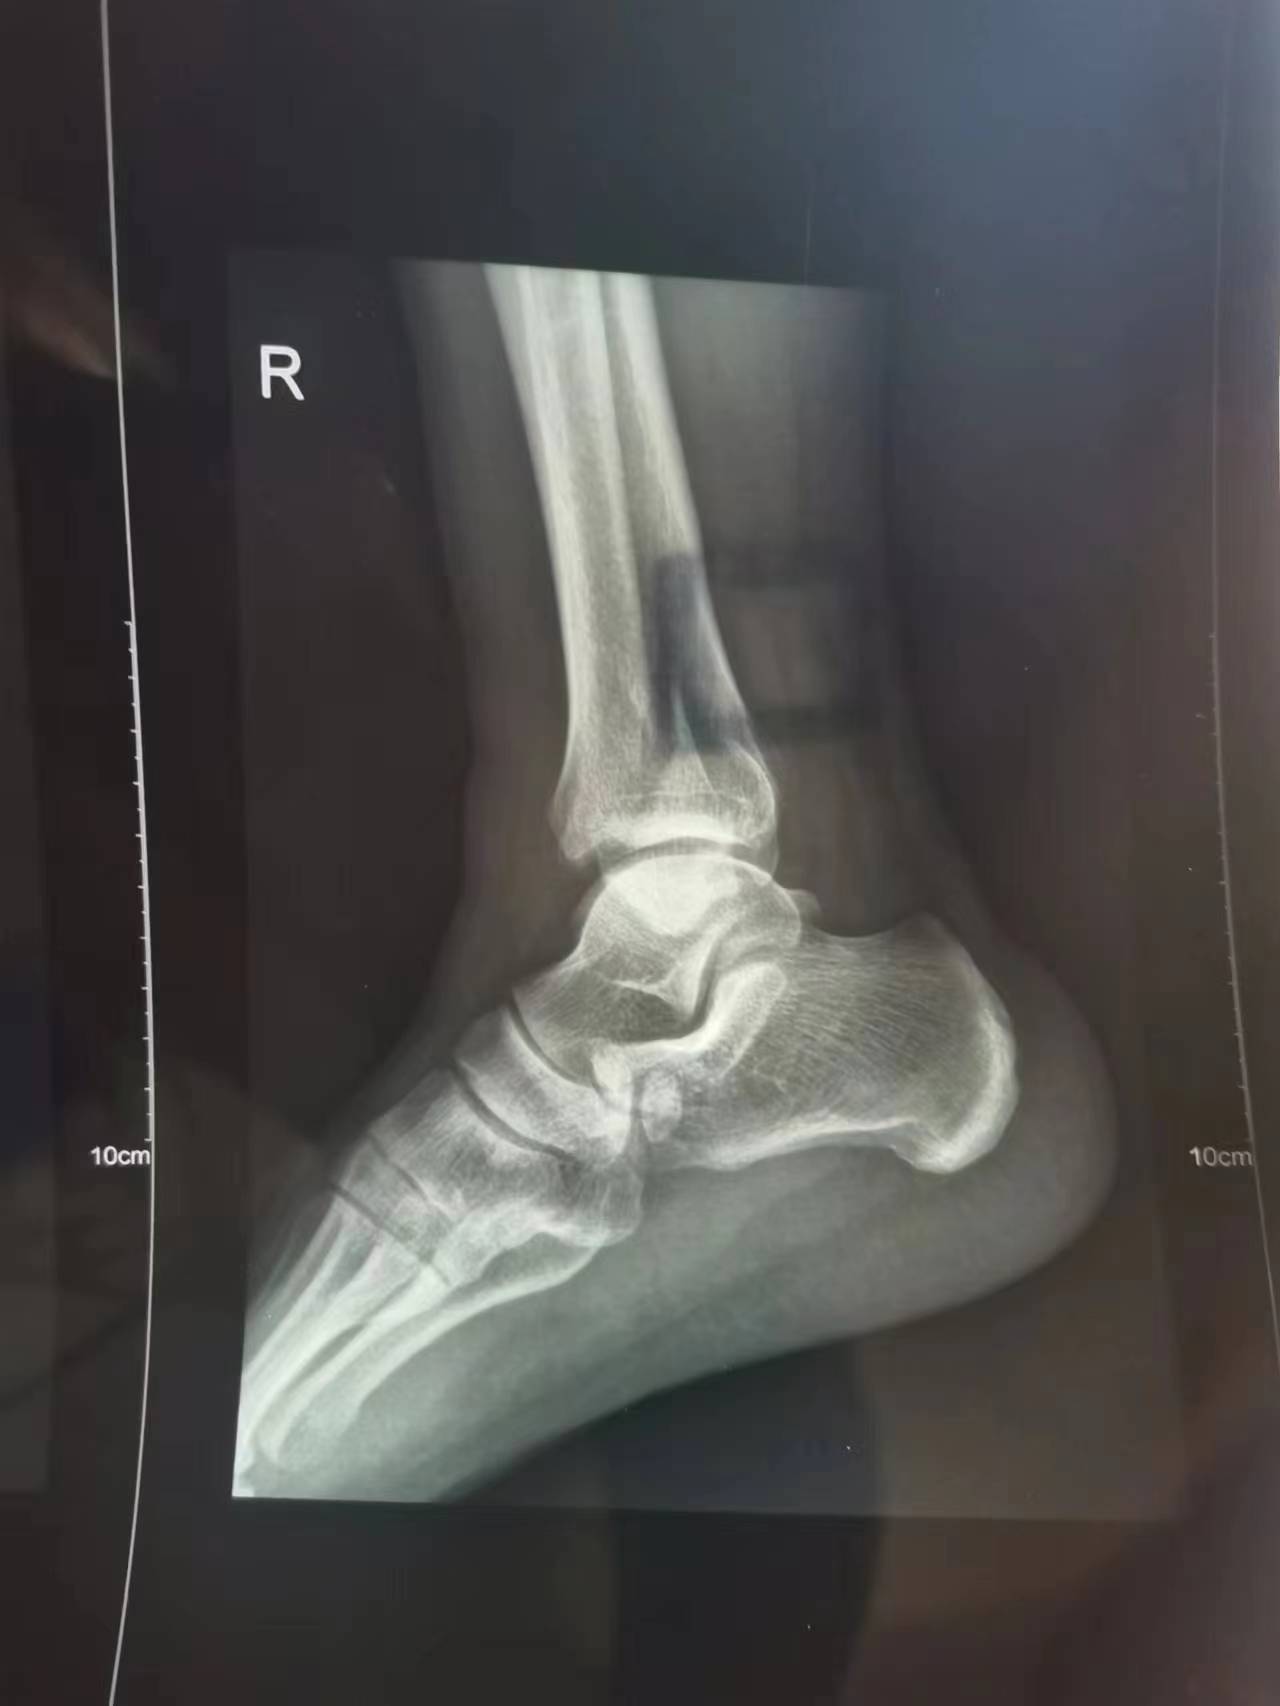

至附近医院急诊拍片:右内外踝骨质断裂、断端错位,右踝关节周围软组织肿胀。余右踝诸组织结构完整,未见明确骨折线;右踝关节未见明显脱位。

这张,左看右看,反正我是看不出来啥